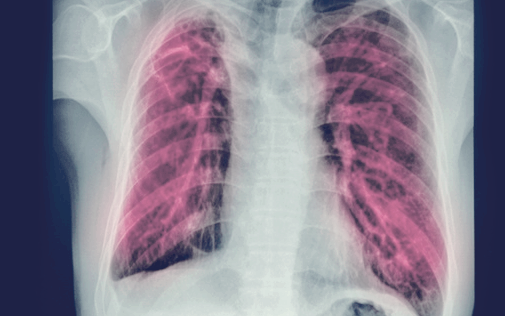

폐렴: 폐포까지 침범하는 하기도 감염

폐렴은 폐의 말단 구조인 폐포(alveoli)에 염증이 발생하는 질환으로, 세균, 바이러스, 진균 등이 원인이 될 수 있습니다. 염증으로 인해 폐포 내에 체액이나 삼출물이 차면서 산소 교환 기능이 저하됩니다.

특히 산소 공급에 영향을 주기 때문에 심한 경우 저산소증으로 이어질 수 있습니다.